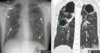

18

A

Patrón intersticial reticular

19

20

21